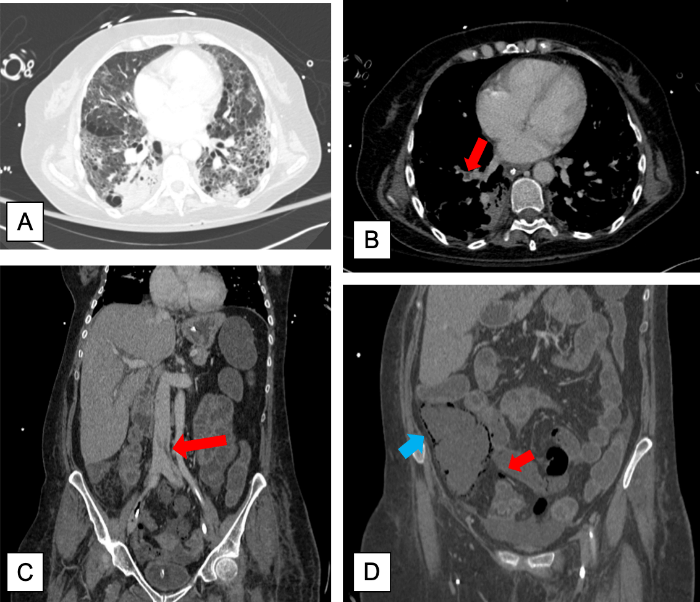

A 57-year-old woman, ex-smoker, with a history of GOLD-I chronic obstructive pulmonary disease, presented with a 7-day productive cough, chest pain and dyspnea. The oropharyngeal swab for SARS-CoV-2 was positive. Lab tests at admission were: D-Dimer 1103 ng/mL, IL-6 47.6, C-reactive protein (CRP) 15.7 mg/dL, Ferritin 254 ng/mL. Arterial blood gas showed severe hypoxemia (PaFiO2 = 58 mmHg), and chest X-ray demonstrated bilobar pulmonary infiltrates. The treatment prescribed was: Ceftriaxone, Azithromycin, Lopinavir/Ritonavir, low-molecular-weight heparin (0,5 mg/Kg) and high flow oxygen therapy. Despite this, her clinical condition deteriorated. A dose of beta-interferon was given, (16UM) and she was transferred to the ICU. She required orotracheal intubation and prone positioning at days 2, 4 and, 6. She developed a persistent multi-organ failure, requiring noradrenaline (maximal dose: 0,9 µg/Kg/min) and renal replacement therapy on day 8. She was treated for a catheter-related bloodstream infection due to C. albicans and tracheobronchitis due to S. aureus . During the two weeks of ICU admission, the respiratory condition progressively improved, decreasing the oxygen FiO2 (from 0.5 to 0.3) and PEEP (from 12 to 6 cm H2O). On the 16th day, she presented with hemodynamic and respiratory impairment. The physical examination revealed abdominal distension. Lab tests showed: severe metabolic acidosis (pH, 6.68), leukocytosis of 13000, alanine transaminase 183 U/l, and CRP 25.89 mg/dL. An urgent thoracoabdominal CT scan reported signs of pneumatosis in the distal ileum and ascending colon suggestive of ischaemia (Figure 1D), with mural irregularity predominantly in the ileum, together with bilateral and multilobar ground glass opacities consistent with the already known COVID-19 infection (Figure 1A).

Figure 1: A) Chest CT scan showing an emphysematous lung with COVID-19 infection: bilateral and multilobar ground-glass opacities with a peripheral distribution, mainly in the lower lobes. B) Filling defect within the pulmonary vasculature in the right lower lobe compatible with pulmonary embolism. C) Filling defect in the inferior vena cava due to a thrombus. D) Intramural gas of the cecum (blue arrow) and mesenteric vein gas (red arrow) caused by mesenteric ischaemia.

An urgent exploratory laparotomy was performed. Ischaemia of the entire right colon, as well as patched ischaemia of the distal-middle ileum, were found (Figures 2A & 2B). A right hemicolectomy and resection of the distal-middle ileum with a terminal ileostomy were performed. During the following hours, the patient deteriorated her multiorgan failure status, which finally resulted in her death. Pathological examination reported: severe ischaemic colitis, with areas of mucosal necrosis and the presence of abundant small-caliber microthrombi in the submucosa and medium-caliber vessels of the mesocolon (Figure 2C), together with moderate inflammatory infiltrates. Re-examination of the CT scan revealed findings consistent with right lower lobe segmental pulmonary embolism (Figure 1B), as well as inferior vena cava filling defects consistent with thrombi (Figure 1C).